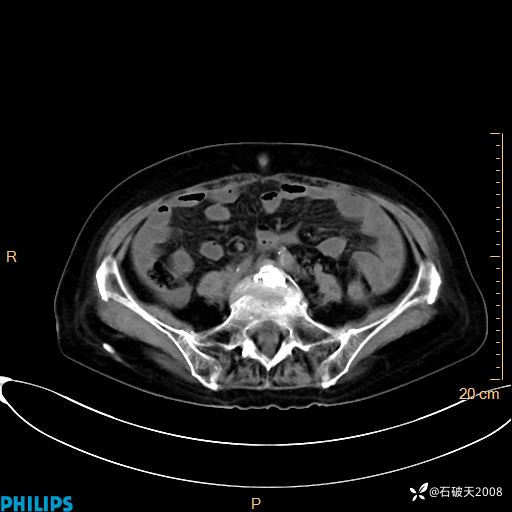

平扫